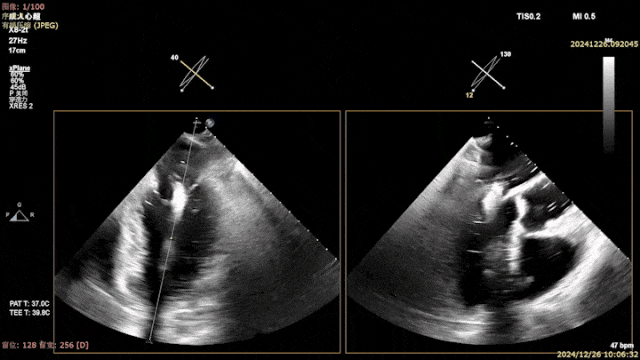

术中导引鞘和二尖瓣夹植入

Trajectory & Orientation

Gripper Down

关闭二尖瓣夹

二尖瓣夹释放后评估